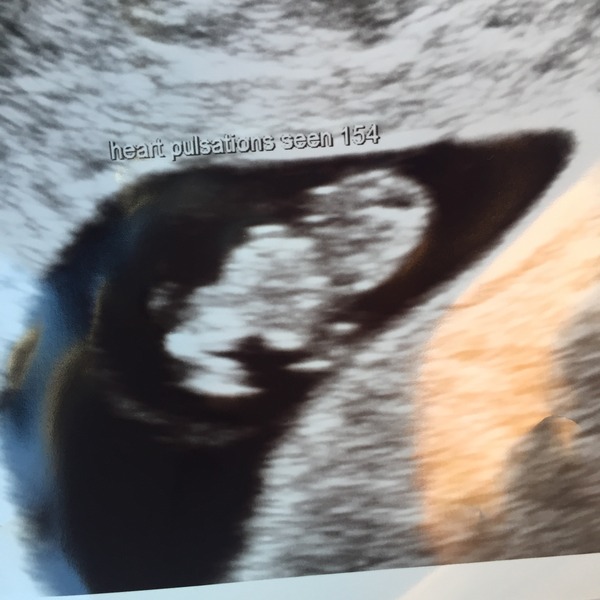

Hi all. Due to my spotting paid for an early scan and thankfully all is looking well. I'm 8+4 today and measurements from the scan are measuring 8 weeks exactly. Heartbeat strong and my right ovary (where the egg released) is partially collapsed and has a little bleed on it - apparently this is due to the pregnancy and will sort itself out but could be the reason for the spotting. The image actually looks like a little baby.

Those of you waiting for scans - just give it time, it's all you can do. We were fearing the worst but so far, so good.

That's an amazing scan for 8 weeks! It really looks like a tiny tiny baby. Was it an internal?

They did an external and it was clear but as I was so worried, she offered to do an internal too which is what that image is from.

It's called a luteal cyst and I've googled it since I got home - apparently rather common.

It was expensive but a wonderful experience, very thorough, they measured the heartbeat, checked both ovaries and tubes, looked for any bleeds, checked my cervix was closed etc.